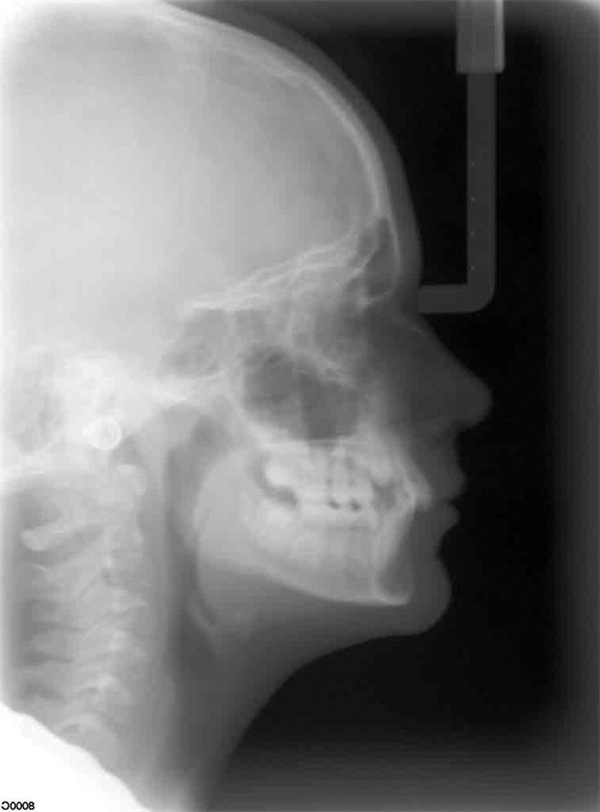

Updated records told a different story. The upper right canine remained fully unerupted, and significant adverse canting of both arches had developed on the right side (Figs. 4–6). Root shortening was visible on the upper right canine, lateral, and central incisors, likely a consequence of prior reluxation attempts to encourage eruption. The upper incisors had also become markedly more proclined over the course of treatment, a known risk when ectopic canines prove resistant to traction. Comparing the pre-treatment and current lateral cephalometric radiographs illustrated just how much incisor angulation had shifted (Figs. 2, 10). Facial photographs suggested some lower-third asymmetry with a right-side deviation, though the lower arch canting appeared to have partially self-corrected after vertical elastics were discontinued (Figs. 7–8).

Fig. 10